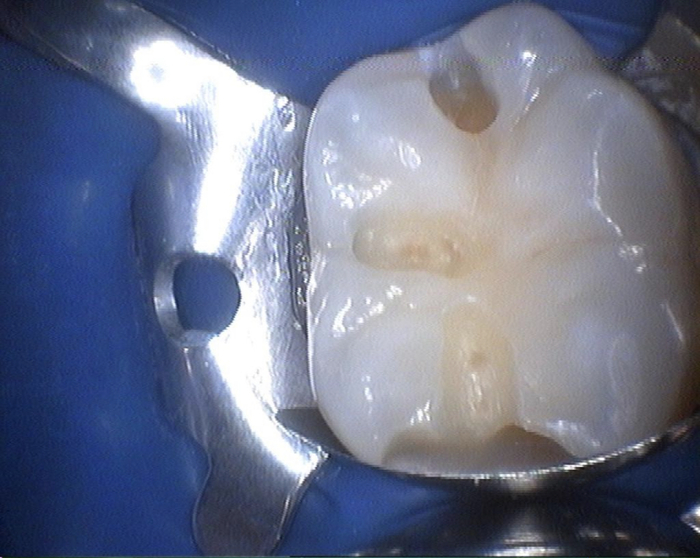

Снимки

Это собственно зуб под удаление молочный

А это тот самый сложный кариес. Как сказала врач БЕЛЫЙ КАРИЕС который очень сложно лечить